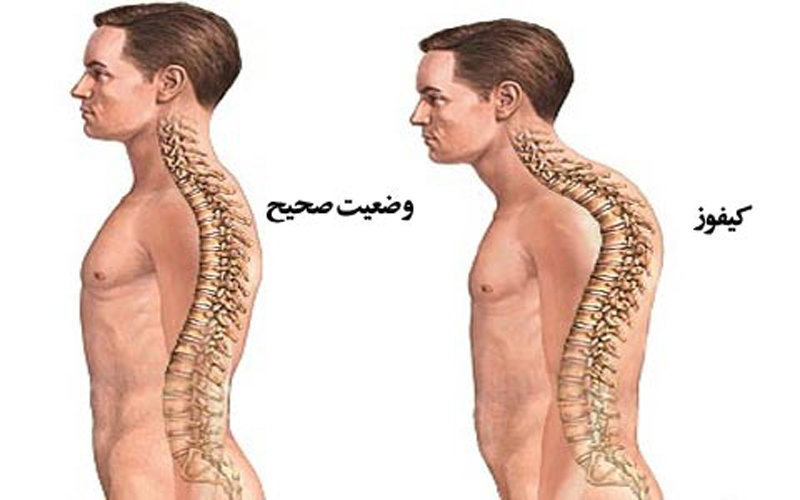

قیمت: 22٬000 تومان - دسته بندی فایل: پاورپوینتپاورپوینت پشت گرد (کیفوز پشتی)

فروش ویژه پاور پوینت حرفه ای پشت گرد (کیفوز پشتی) با تخفیف استثنایی فقط 49 هزار تومان تعداد اسلاید: 11 اسلاید